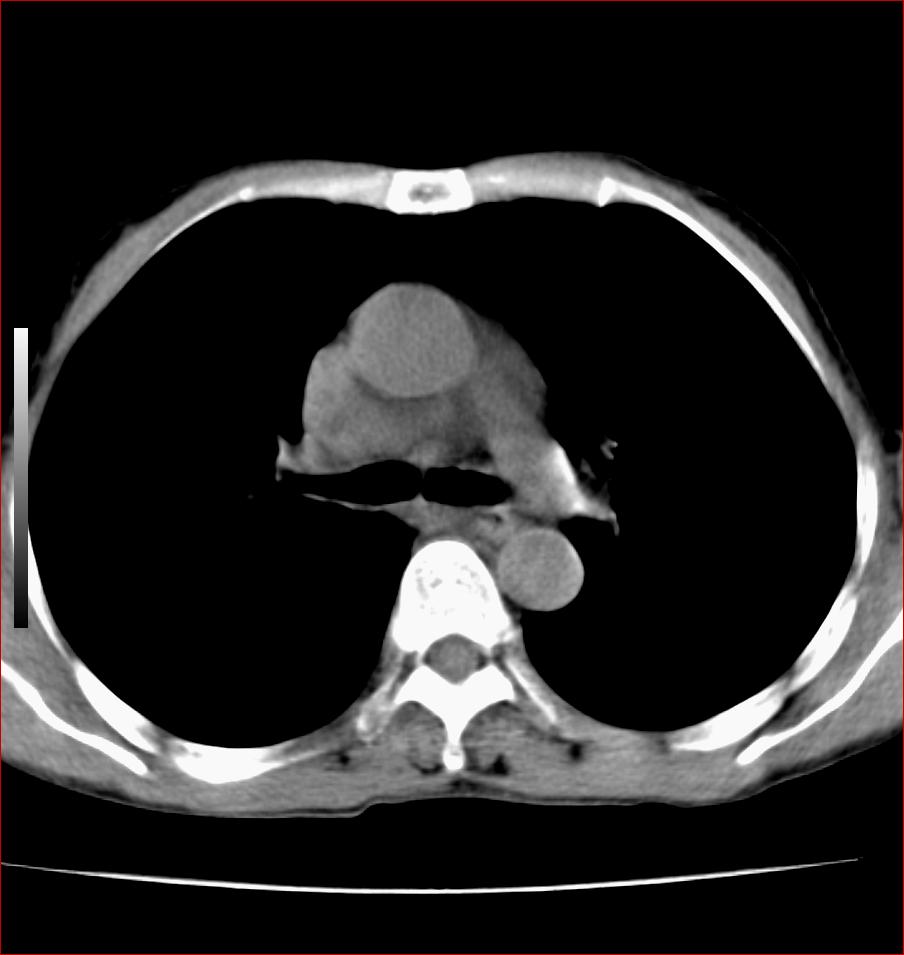

标题: CT17110:F56Y,纵隔囊肿;胸腺?淋巴?请各位老师看看 [打印本页]

标题: CT17110:F56Y,纵隔囊肿;胸腺?淋巴?请各位老师看看

女性患者 56 咽痛伴声嘶10+天入院。

右上纵隔囊性占位性病变;考虑支气管囊肿可能。

病变紧贴气管右壁,两者相互压迫,考虑支气管囊肿!

见相互挤压征,考虑气管囊肿,建议ct增强扫描

纵隔前肠性囊性,支气管囊肿可能性大